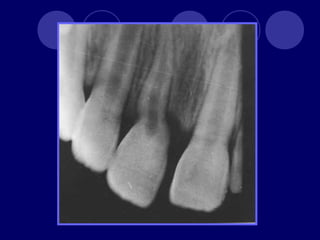

DENS IN DENTE Dienteinvaginado, invaginación de las células del epitelio interno del órgano del esmalte. Más frecuente en dientes anteriores superiores, lateral, central, 2:1 Esmalte, dentina (cemento) Radiográfico

 Etiología  Fusióndental  Invaginación activa (campana)  Retardo pasivo  Desplazamiento  Traumática o infecciosa

 Clasifica en: Diente invaginado coronal  Con forma coronaria normal • Que no sobrepasa la corona • Sobrepasa la corona y se alarga en raíz • Invaginación radicular con fondo invaginado abierto • Apertura lateral  Forma coronaria anormal • Que no sobrepasa la corona • Sobrepasa la corona y se alarga en raíz • Invaginación radicular con fondo invaginado abierto • Apertura lateral  Diente invaginado radicular